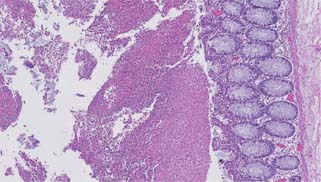

Figure 2: Low power image of colonic mucosa with fibrinopurulent exudate and crystals (Hematoxylin and eosin, 2× magnification).

Figure 3: Medium power image of colonic mucosa with fibrinopurulent exudate and crystals (Hematoxylin and eosin, 5× magnification).